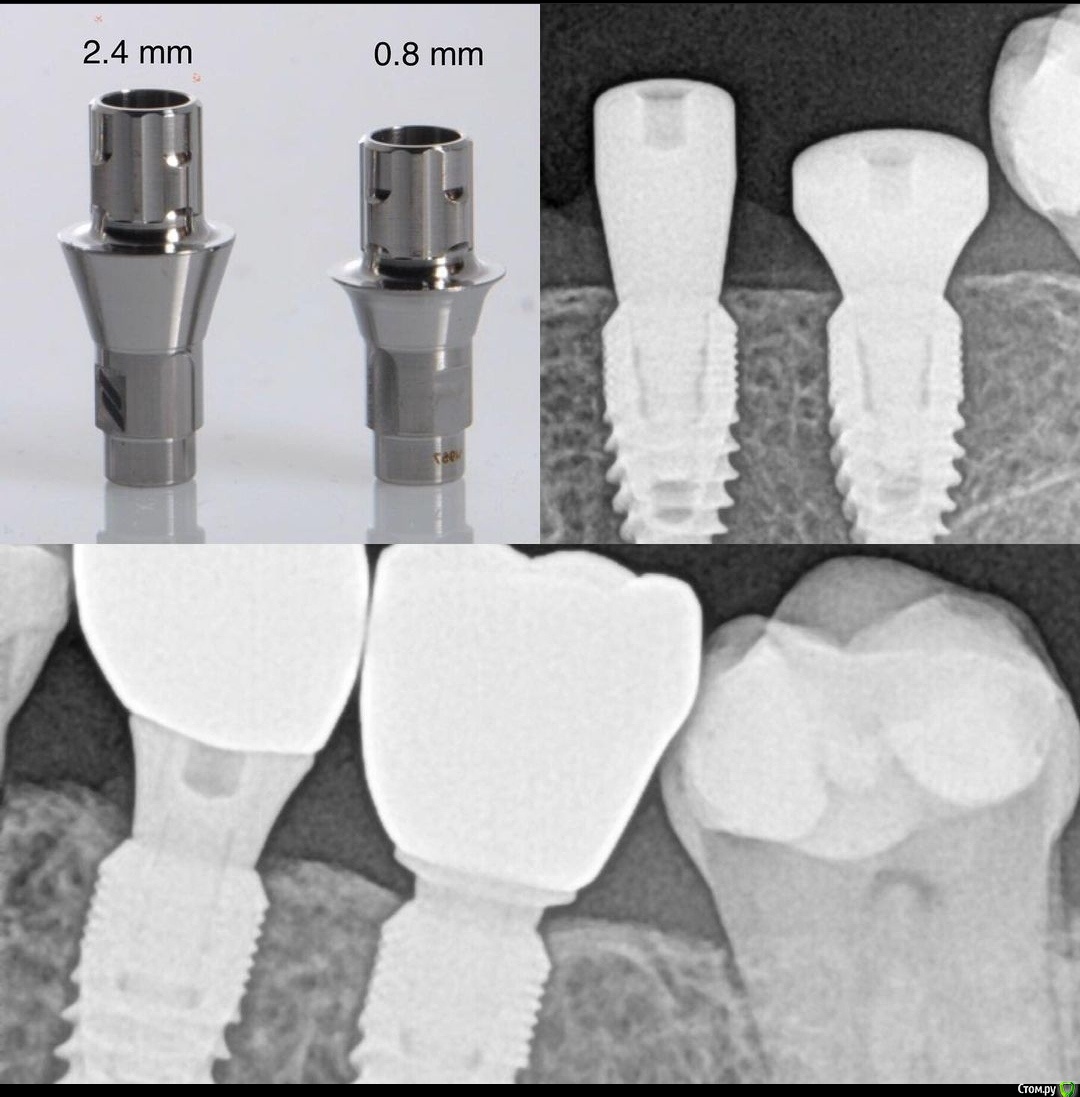

колесников Опубликовано 17 декабря, 2020 Поделиться Опубликовано 17 декабря, 2020 (изменено) Какой фдм стоял? 1 мм абатмент нормально ,если рабочий фдм был 6х2,7х3Уступ абатмента по отношению к костным пикам и гребню. Если основание шире финального фдм,лучше делать послабляющие подсечки в десневой шахте,рассекать запирающее кольцо Изменено 17 декабря, 2020 пользователем колесников Ссылка на комментарий

Дмитрий М Опубликовано 20 декабря, 2020 Поделиться Опубликовано 20 декабря, 2020 Сам такие не люблю, т.к. вероятность упереться краем в кость повышается, но у этой системы временные абатменты только эти. Кстати, согласно Т. Линкевичусу, высота основания не имеет роли, если достаточно десны над имплантатом (3+ мм) и трансгингивальная часть из диоксида циркония. спиливать вручную или просить техника спилить, придать диаметр уступа как у формирователя, полировка до блеска.высота основания не важна если диаметр этого основания не шире чем у формирователя 1 Ссылка на комментарий

kramer Опубликовано 20 декабря, 2020 Автор Поделиться Опубликовано 20 декабря, 2020 Ну и юбки долой, конечно!) если диаметр этого основания не шире чем у формирователя Вопрос с юбками интересный. Уступ не должен быть по крайней мере шире самого имплантата, иначе будет ишемия и т.д. - это нам подсказывает логика. Я и сам не люблю такие. Но исследования это опровергают) 1 Ссылка на комментарий

Дмитрий М Опубликовано 20 декабря, 2020 Поделиться Опубликовано 20 декабря, 2020 Вопрос с юбками интересный. Уступ не должен быть по крайней мере шире самого имплантата, иначе будет ишемия и т.д. - это нам подсказывает логика. Я и сам не люблю такие. Но исследования это опровергают) по ширине уступа и импланта согласен, это понятно, более широкий и не сядет )))но в данном случае суть именно в пространстве для мягких тканей, возможно 1мм уступом передавлен "соединительно тканный этаж" я так думаю ))))) тоже не люблю 1мм основания, но как говорится в анекдоте за неимением горничной имеем дворника ))) 1 Ссылка на комментарий

колесников Опубликовано 20 декабря, 2020 Поделиться Опубликовано 20 декабря, 2020 (изменено) Вопрос с юбками интересный. Уступ не должен быть по крайней мере шире самого имплантата, иначе будет ишемия и т.д. - это нам подсказывает логика. Я и сам не люблю такие. Но исследования это опровергают) не знаю о каких Вы исследованиях и Линкявичюс по моему совсем иное проповедует,ни какое исследование не сможет подтвердить положительные свойства 1мм уступа для конической системы и субкрестальной позиции платформы. Десна отвоюет свои 2мм за счёт резорбции кости. Эти исследования могут быть верны только для имплантов с крестально и супракрестальной позицией. Изменено 20 декабря, 2020 пользователем колесников Ссылка на комментарий